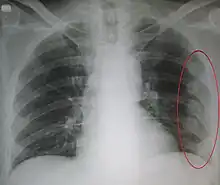

| An X ray showing multiple old fractured ribs of the person's left side as marked by the oval | |